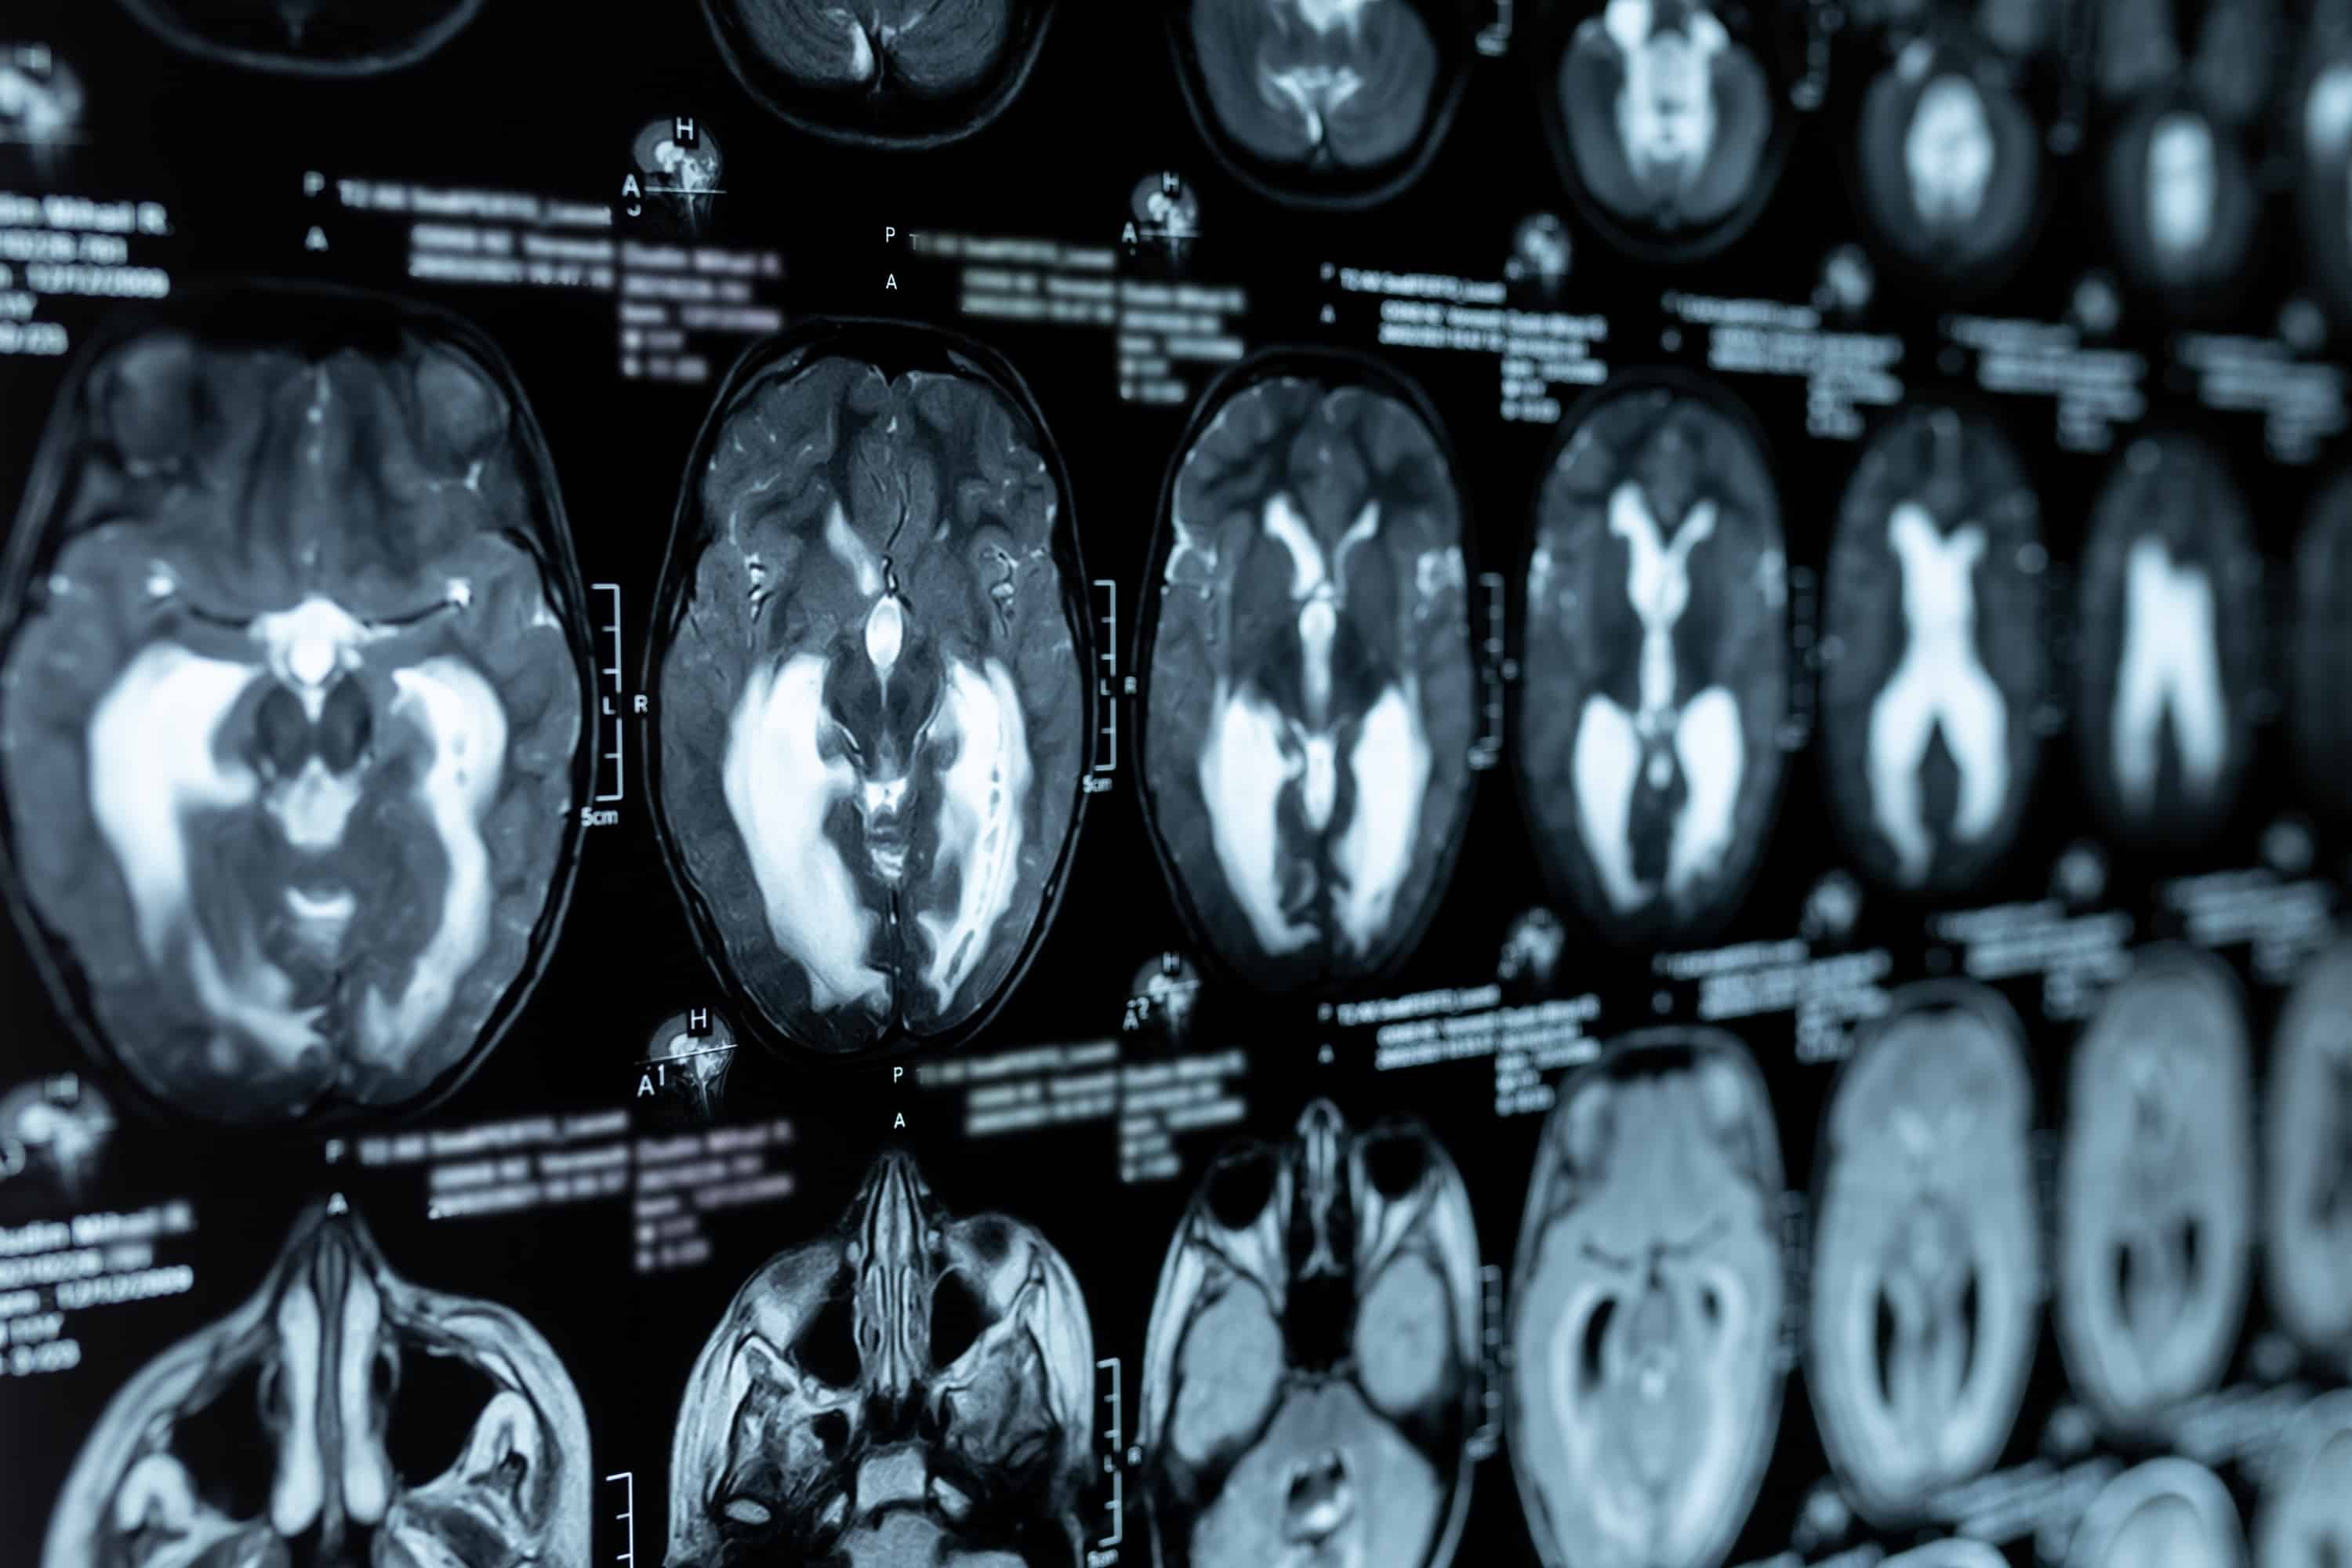

Magnetska rezonancija (MR) mozga je pretraga kojom se prikazuju sve strukture, ovom metodom jasnije i detaljnije od drugih metoda snimanja, bez korištenja ionizirajućeg zračenja.

MR mozga koristi se za dijagnosticiranje:

- tumora mozga

- moždanog udara

- infekcije

- razvojnih anomalija

- hidrocefalusa

- uzroka epilepsije (konvulzija)

- krvarenja u mozgu

- multiple skleroze

- poremećaja oka i unutarnjeg uha

- poremećaja hipofize

- vaskularnih promjena (aneurizma, arterijska okluzija ili venska tromboza)

- promjena hipofize

- upale sinusa

- ozljeda glave

- glavobolje

- vrtoglavice

- upale sinusa ili

- bolesti temporalne kosti.